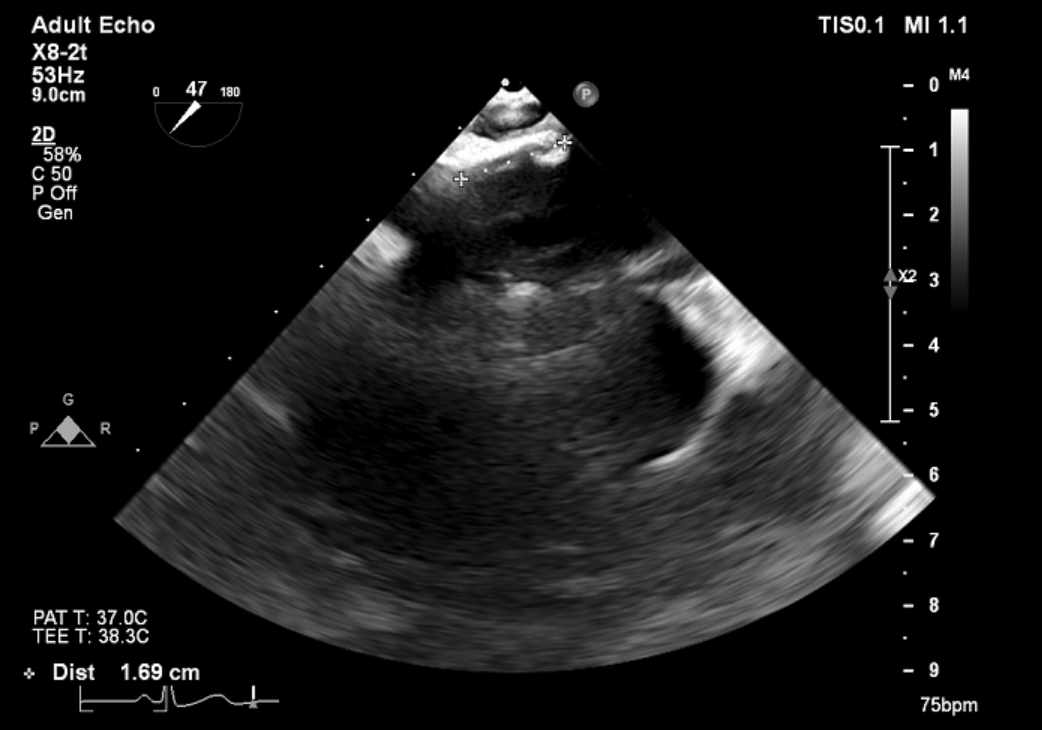

术前TEE评估

原发性二尖瓣反流(DMR),后叶P3区脱垂,反流程度4+,EROA 0.40cm2、RV 39ml;二尖瓣瓣口面积5.37cm²;二尖瓣前叶(A3)长度14.0mm,二尖瓣后叶长度(P3)长度12.2mm,脱垂宽度8.2mm,脱垂高度1.4mm;RA 2.9cm ,LA 3.6cm,左室射血分数LVEF56%,术前测量最大房间隔穿刺高度4.0cm

患者全身麻醉消毒铺巾后,建立右侧股静脉入路,在经食道超声指导下房间隔穿刺。根据要求,房间隔穿刺高度至少需要4.0cm,患者本身的解剖结构,左房和右房都比较小,如果选取卵圆窝靠后,靠中上的位置穿刺点高度只有2.6cm,是无法完成整个手术操作的,那么想要在安全的前提下获得更充分的房间隔穿刺高度,考虑选择在房间隔肌部穿刺,采用穿刺针的内芯,PCI导丝,甚至电刀穿刺的方式,都无法突破房间隔。患者的卵圆窝松弛,肌部又硬,苏晞院长团队决定在肌部与膜部交界的位置穿刺,经过精细调整,精准定位,最终以3.64cm的极限高度突破房间隔,而后将MitraClip™可操控导引导管(SGC)送入左心房。